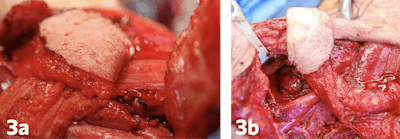

Figure 3a and 3b. Laryngopharyngeal defects closed with the supraclavicular artery island flap.